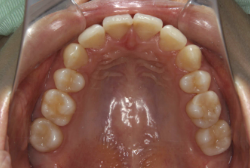

叢生(そうせい)

凸凹な歯並びのことを叢生といいます。矯正歯科に来院する患者様の主訴の中で、最も多いのが「配列の凸凹を真っ直ぐにしたい」というものです。歯の大きさと顎の大きさの調和がとれていないことが原因です。

凸凹を主体としたケースの場合、当院の平均治療期間は18ヶ月ですので、このケースは少し長めに経過しました。理由の一つは凸凹の程度がかなり重症だったと言うことですが、もう一つは、右下第2大臼歯が45度くらい前傾していたため、それを整直化させるために時間を要したと考えています。いずれにしても最終結果は大変よい状態と思います。

治療前は並びが乱れて見た目が悪いというのはもちろん問題ですが、歯科医学的に一番困るのは噛み合わせが悪いという点です。上下の犬歯(3番目の歯)は、上下的に離れた位置にあるため接触することができません。つまり歯としては存在していても、歯としては機能していないということです。